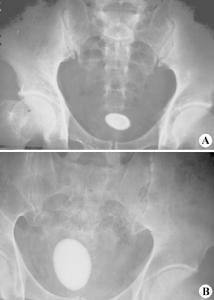

膀胱鏡於成人檢查確診較重要,小兒由於不合作,檢查操作較困難,甚恐引起膀胱尿道損傷及穿孔。最常用的診斷是腹部X光單片,因大多數結石在X線下顯影。膀胱結石主要在膀胱中形,成但也有自上泌尿道降入膀胱內而逐漸增大。一旦確診膀胱結石應積極治療。

8、X線檢查 膀胱區平片能看到不透光的結石陰影。

1、膀胱區攝X線平片多能顯示結石陰影。